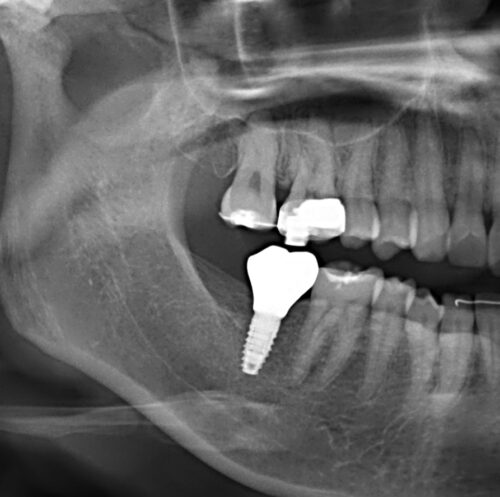

30代女性。矯正歯科にて全額矯正を行った際、下顎7番の長期欠損による上顎7番の挺出も改善。最終的に欠損部をどうするかという話になり、矯正医からインプラント治療を勧められ当院に来院された患者さんです。

下顎7番にインプラントを埋入。

上部構造を装着しました。